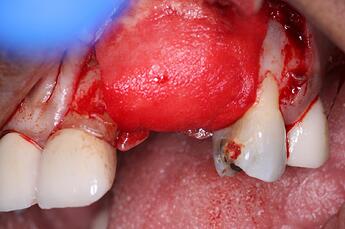

Next, we folded over the OsseoSeal collagen membrane to cover the bone and extend onto the native bone margins. It is crucial to try to cover everything and create a large enough space for the graft material to heal.

Finally, we sutured the site using Chromic Gut sutures. It is critical in GBR to get primary closure. In this particular case because of how much bone volume we are adding, a very deep periosteal release was done we we could pull over all the tissue from the buccal and suture the site as passively as possible. For more information this suturing technique, please see: Bone Regeneration of Extensive Socket Defects with Immediate Implant Placement